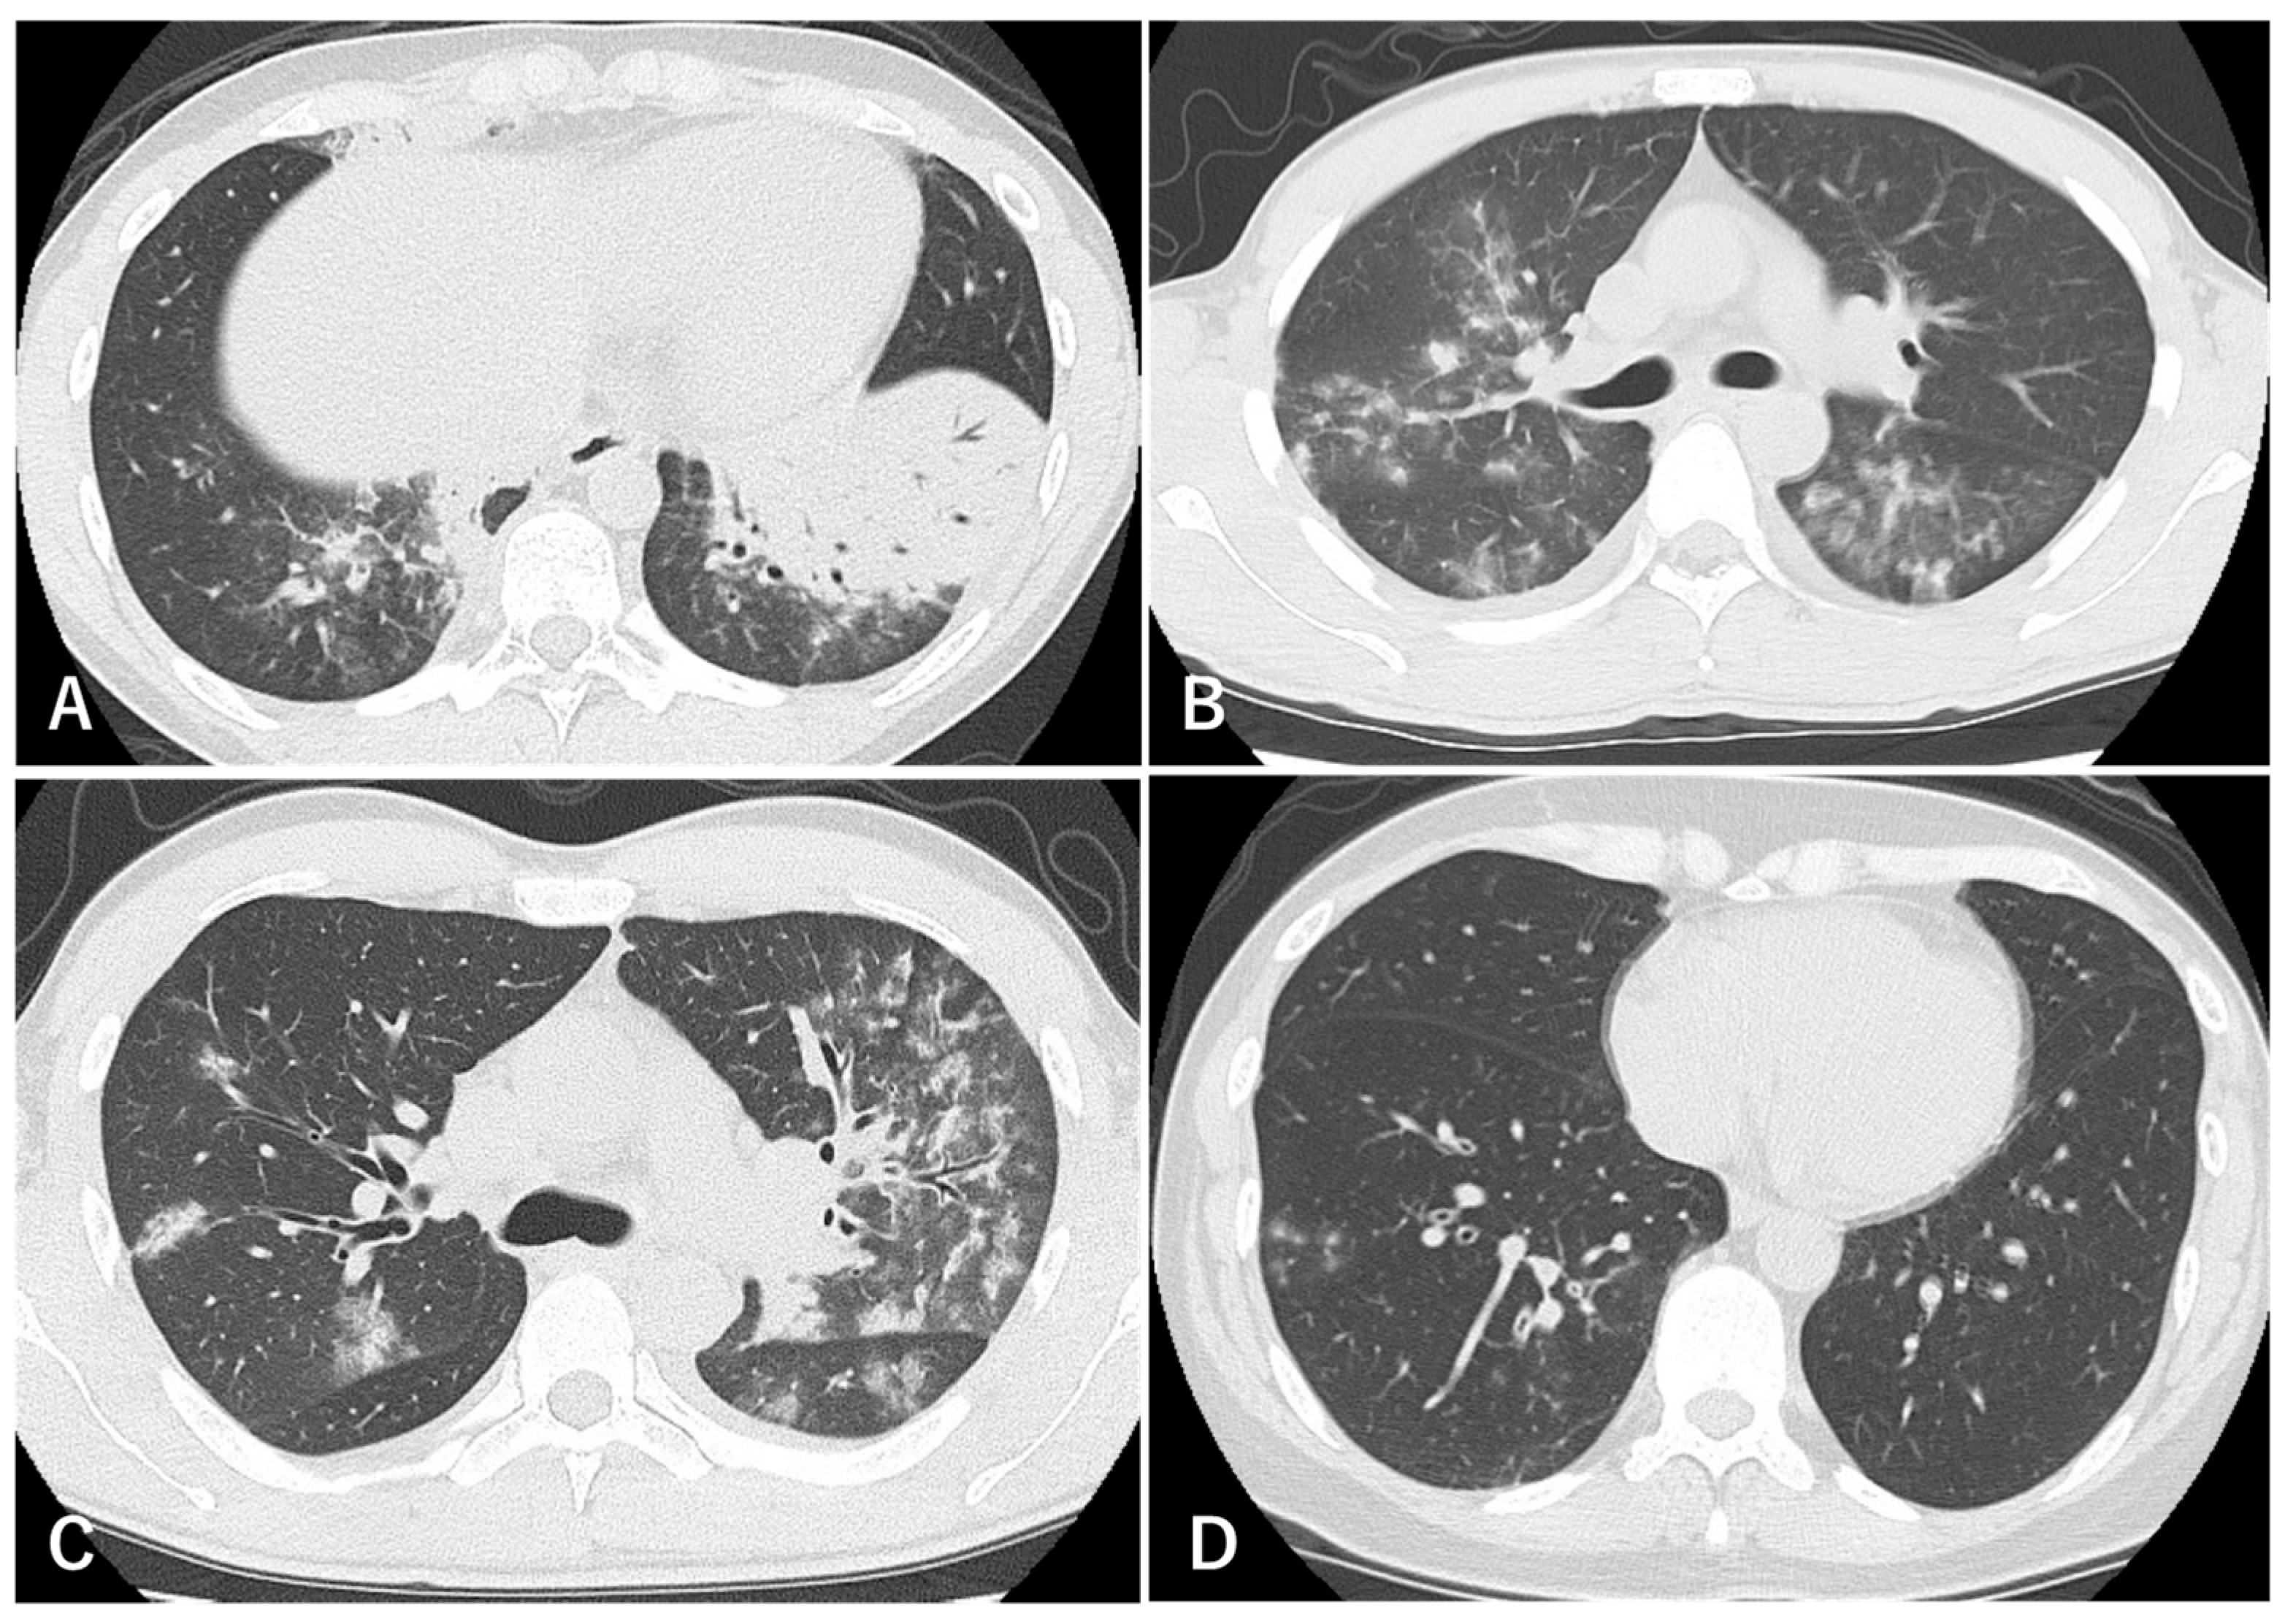

7. Radiological Findings